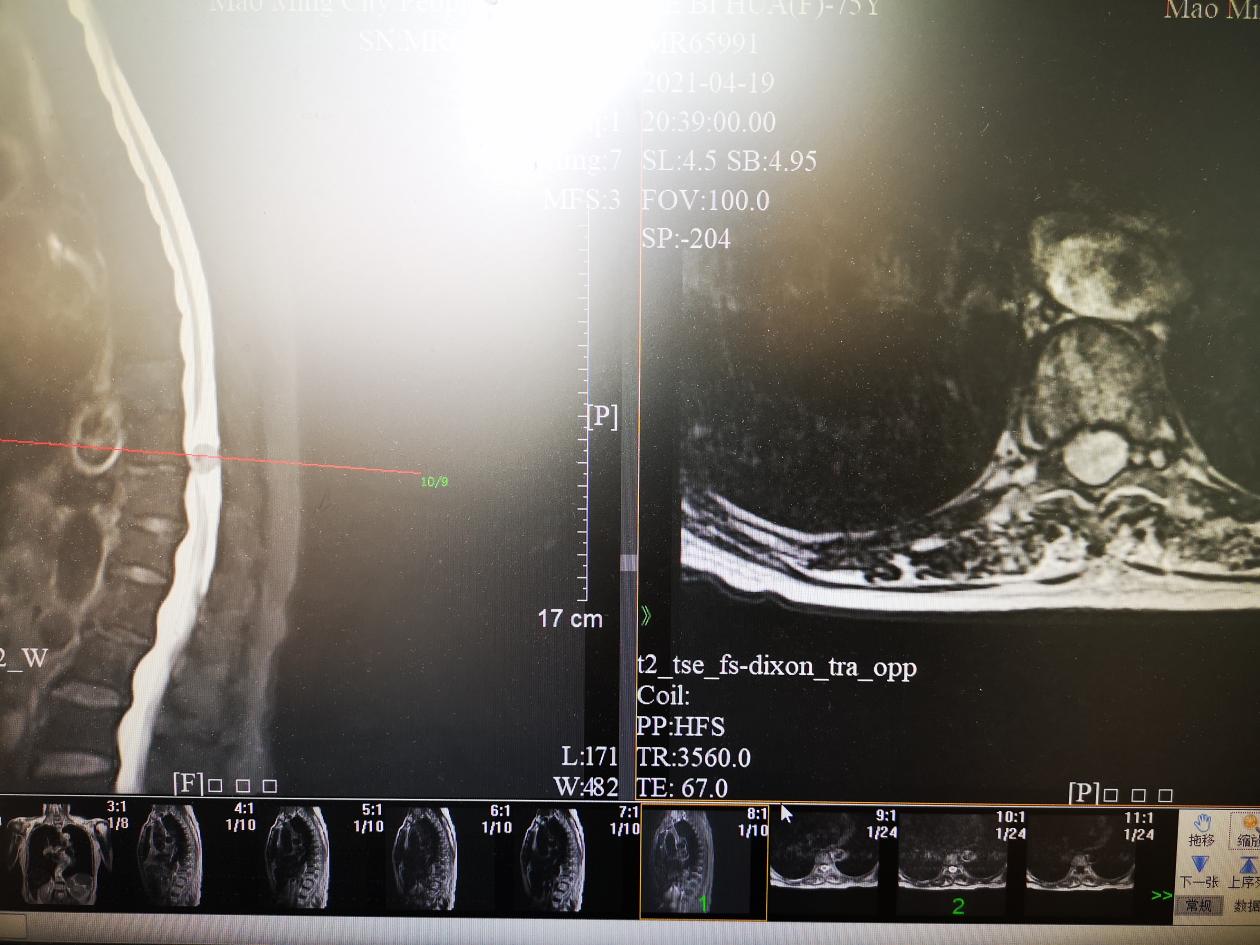

“从核磁共振片上看到,病人的胸椎管内肿瘤体积较大,已经占据了椎管横截面的90%。肿瘤对脊髓压迫较重,但病人除了日渐加重的双侧下肢麻木与无力以外,并没有出现瘫痪现象,所以早期没有得到应有的重视,”赵斌修博士就病人的情况分析,“现在病人没有出现完全瘫痪,但随着肿瘤的继续增大,完全瘫痪是迟早的事情。因此,当务之急是尽早手术切除肿瘤、挽救病人的身体功能。”